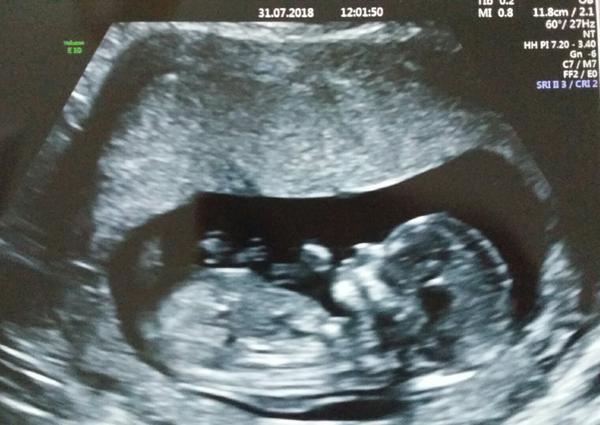

@lenkatorka to je husta fotka 😍 , gratuluju, to uz je normalni clovicek ❤

@skretik taky jsem si říkala ,ze to už je člověk ❤

@lenkatorka ja jdu zitra, tak jsem taky zvedava, co uvidime a jestli bude vse v poradku, snad se mi tam to mimi neupeklo :D